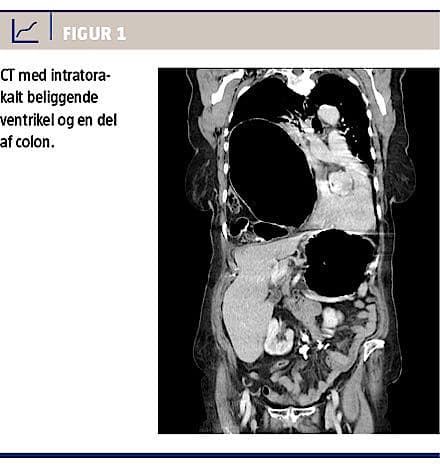

med herniering af ventriklen gennem defekten i diafragma, senest en måned forud for dette forløb. Symptomerne var åndenød, svære øvre abdominalsmerter og opkastninger. En CT viste en intratorakalt beliggende ventrikel og en del af colon (Figur 1). Man behandlede tilstanden konservativt med ventrikelsonde, og hun blev udskrevet til planlagt operation en måned senere. Der blev foretaget laparoskopisk procedure, hvor man i diafragma fandt en 10 × 5 cm stor defekt, som var lokaliseret anteriort og til venstre for hiatus oesophageus. Der var herniering af ventriklen, højre del af colon og en større del af tyndtarmen i højre hemithorax. Indholdet kunne umiddelbart reponeres. Defekten i diafragma dækkede man med en Bard Composit E/X-meche (10,2 × 15,2 cm) og fæstnede den dels med Protacs (5 mm), dels med Goretexsutur. Grundet vævstensionen og defektens alder var det ikke muligt at adaptere kanterne med sutur alene.